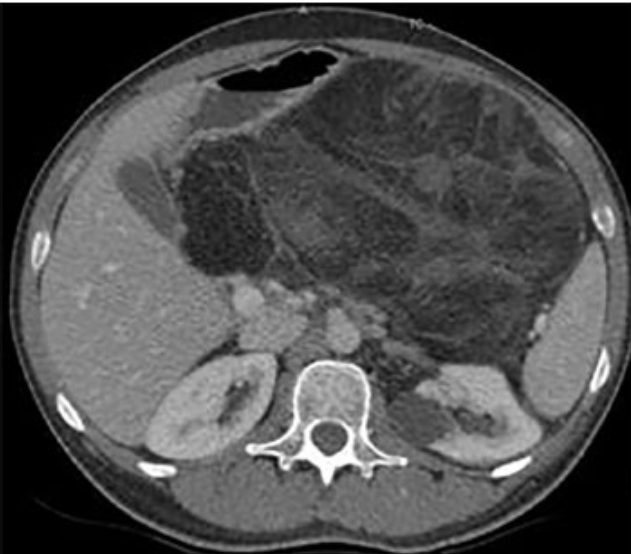

B. Sarcoma de Retroperitônio:

São tumores silenciosos que crescem muito antes de gerar sintomas (efeito de massa, constipação). O diagnóstico costuma ser tardio.

- Imagem: Tomografia de abdome/pelve.

- Biópsia: NÃO! Evita-se a biópsia percutânea pelo alto risco de disseminação tumoral no peritônio. A biópsia só é indicada se o tumor for irressecável (para guiar quimioterapia) ou se houver dúvida diagnóstica (ex: suspeita de linfoma).

- Conduta: A cirurgia é programada com base na imagem.